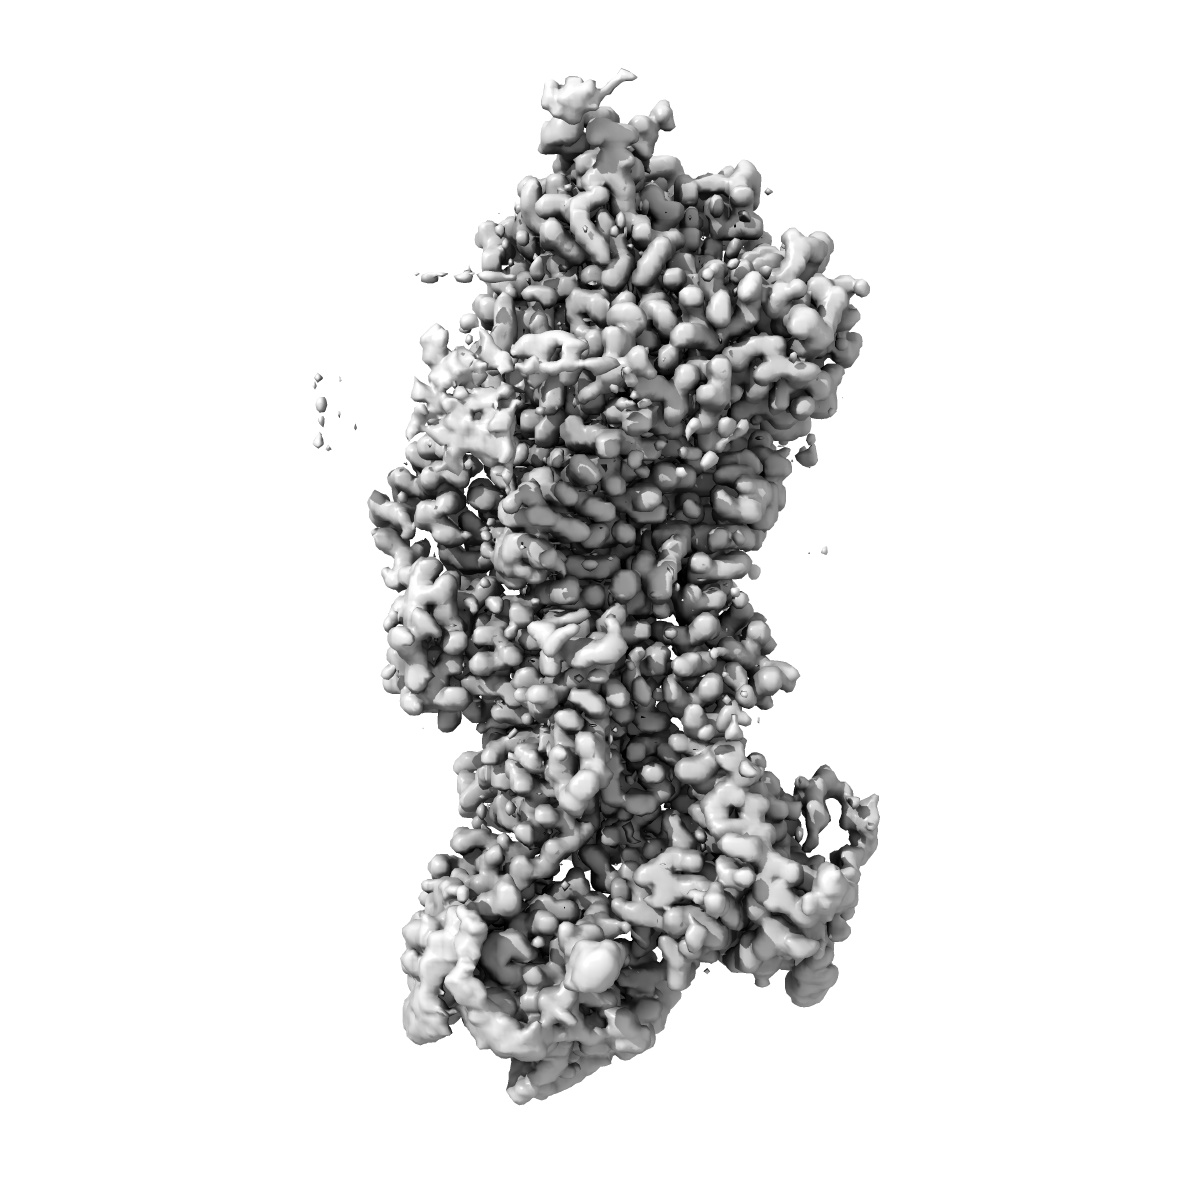

This entry was superseded by EMD-70618.Cryo-EM structure of the C. neoformans lipid flippase Apt1-Cdc50 bound with butyrolactol A in the E2P state

Single-particle2.72 Å